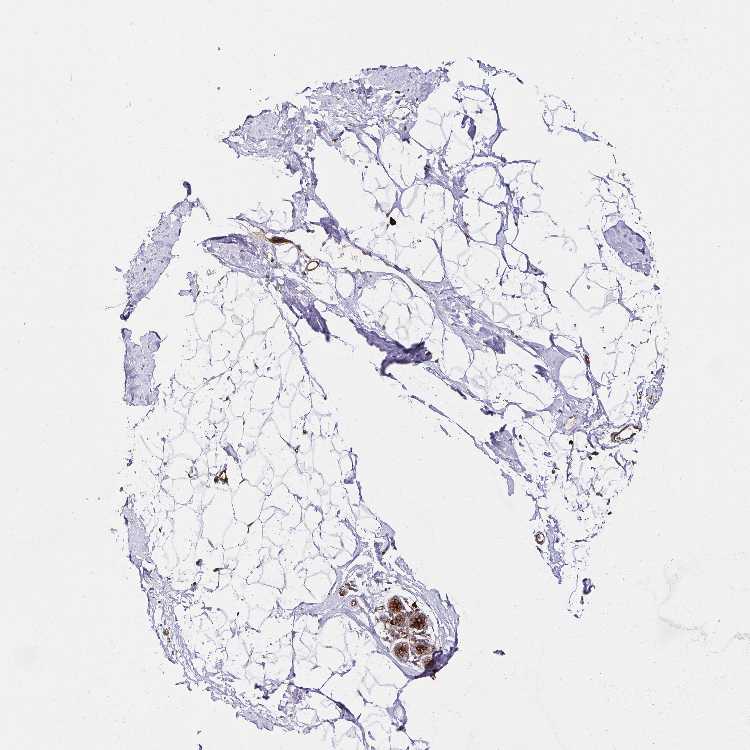

BREAST - Antibody stainingi

Antibody staining in the annotated cell types in the current human tissue is reported as not detected, low, medium, or high, based on conventional immunohistochemistry profiling in selected tissues. This score is based on the combination of the staining intensity and fraction of stained cells.

Each image is clickable and will lead to virtual microscopy that enables deeper exploration of all samples and also displays staining intensity scores, fraction scores and subcellular localization as well as patient and tissue information for each sample.

Antibody HPA045821Antibody HPA054352Antibody CAB012229

Myoepithelial cells MediumMediumMedium